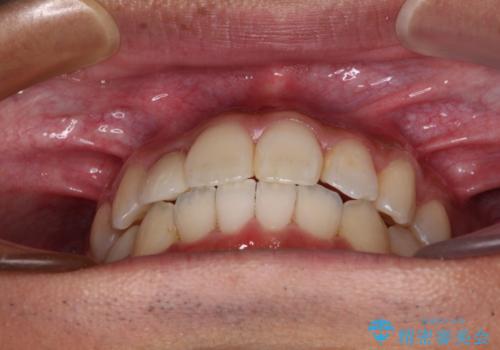

【モニター】左右のクロスバイトをインビザラインできれいに改善

下顎の歯列弓に対して上顎歯列弓がやや小さく、側方の歯を中心にクロスバイトが見受けられました。

奥歯の咬み合わせは接触が少なく物足りないように見えますが、患者様としては十分に咬むことができるとのことでした。